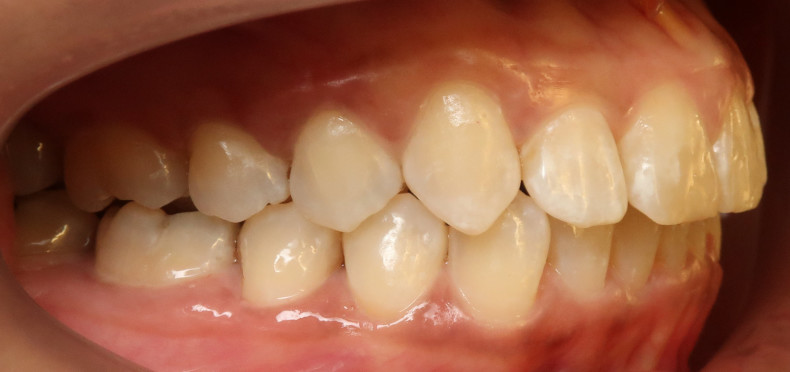

Der intraorale Befund (Abb. 2a–e) sowie die Modellanalyse (Abb. 3a–e) zeigten neben dem Diastema mediale im Oberkiefer vor allen Dingen eine Anteinklination und Supraokklusion beider Fronten. Besonders anterior wiesen beide Zahnbögen eine transversale Enge auf. Dies zeigte sich in einem deutlichen Unterkieferfrontengstand mit Labialkippung des Zahnes 41. Neben Abrasionen und Schlifffacetten, vor allem in der Front, waren auch vereinzelt Gingivarezessionen erkennbar. An Zahn 11 lag eine Schmelzfraktur der Inzisalkante vor. Durch die zwangsgeführte Laterognathie ergab sich eine Mittellinienverschiebung nach rechts von 3 mm. Eine beidseitige Distalokklusion bei vergrößerter sagittaler (6 mm) und vertikaler (5 mm) Stufe war erkennbar. Aufgrund der deutlichen transversalen Zahnbogenenge im Unterkiefer ergab sich links eine Tendenz zum Scherenbiss.